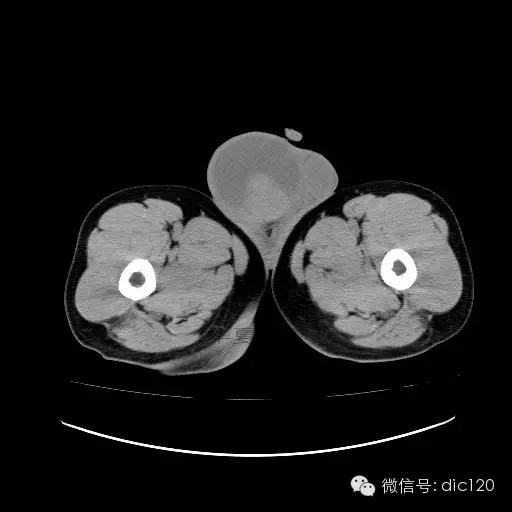

【影像表现】

青年男性,右侧睾丸肿大,边界清晰,增强后睾丸不均匀中度强化,内可见多灶囊变坏死区,动脉期肿块内有细小动脉血管显示,延迟期可见分隔样强化,鞘膜囊可见积液。

定位定性:右侧睾丸恶性肿瘤。

【影像诊断】

右侧睾丸精原细胞瘤,右侧睾丸鞘膜积液。